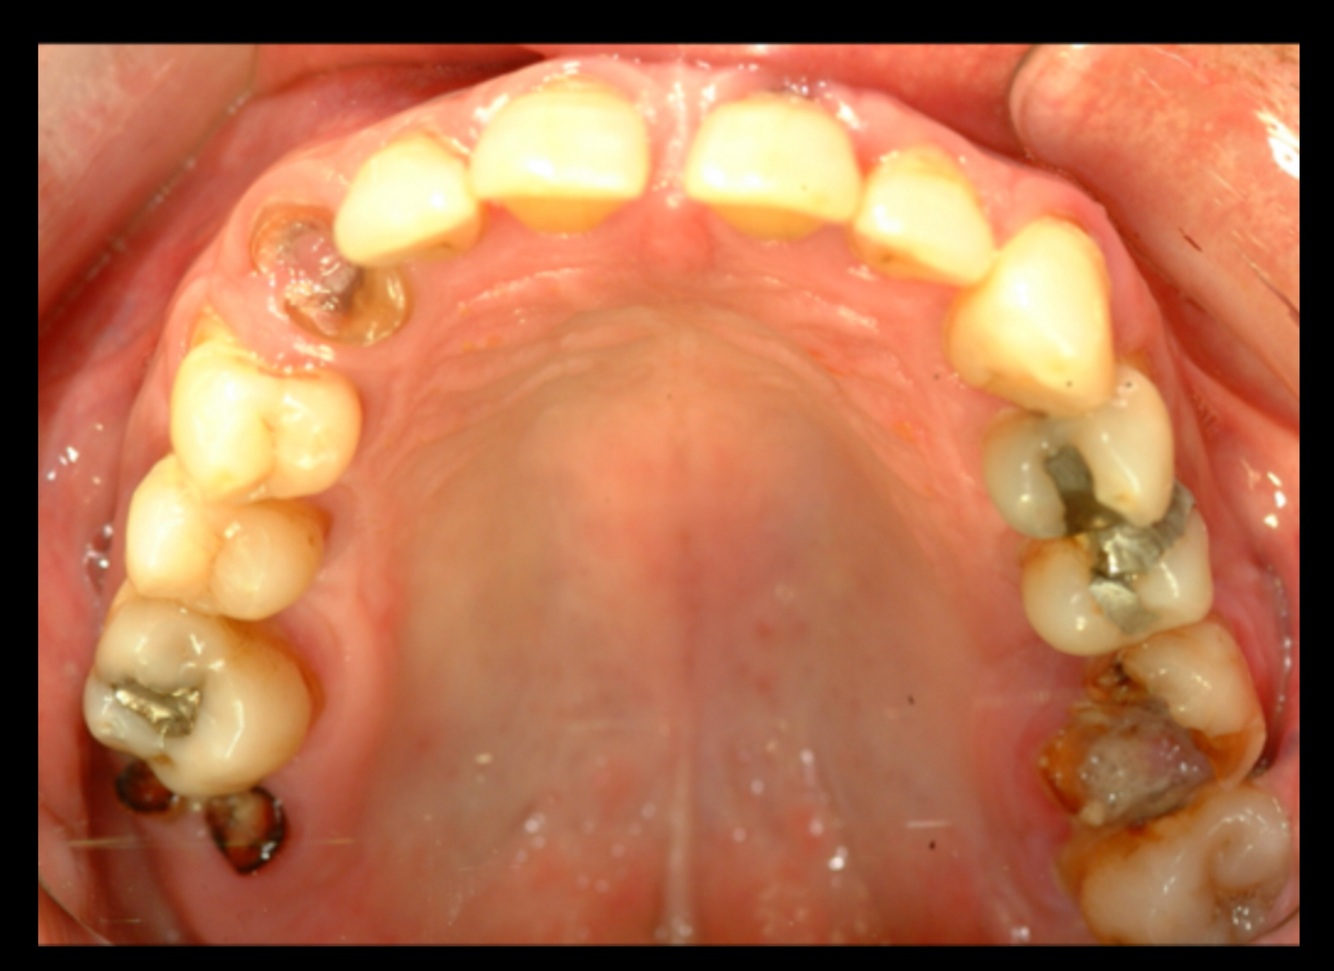

16

Q

Identify the restored tooth using both the long-hand and FDI notation systems

A

Upper right first molar,16